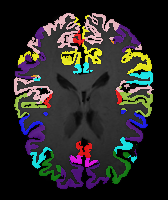

Image Manual Seg DA-1 Mono-21 DA-21 Mono-65 Refer to caption Refer to caption Refer to caption Refer to caption Refer to caption Refer to caption

Figure 2:  Examples of knee MRI registration (top) and brain MRI segmentation (bottom) results. Top: The first two columns are the moving image/segmentation and the target image/segmentation followed by the warped moving images (with deformation grids)/segmentations by different models. Bottom left to right: original image, manual segmentation, and predictions of various models. Mono-i𝑖i and DA-i𝑖i represent the mono- and DA models with i𝑖i manual segmentations respectively.

Image Manual Seg DA-1 Mono-5 DA-5 Mono-200 Refer to caption Refer to caption Refer to caption Refer to caption Refer to caption Refer to caption

Figure 4: Examples of brain MRI registration (top) and knee MRI segmentation (bottom) results. Top: The first two columns are the moving image/segmentation and the target image/segmentation followed by the warped moving images/segmentations by different models. Bottom left to right: original image, manual segmentation, and predictions of various models. Mono-i𝑖i and DA-i𝑖i represent the mono- and DA models trained with i𝑖i manual segmentations respectively.